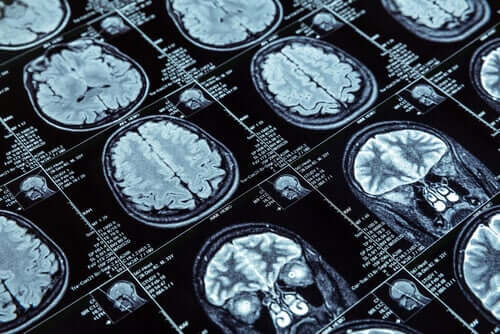

За да извършат изследването, бе направен ядрено-магнитен резонанс на повече от 600 души, които бяха на 45 години по време на теста за образна диагностика. Тези 600 души са част от по-голяма единица, състояща се от повече от 1000 души. Новозеландците ги изучават от детството им.

Те измерват дебелината на мозъчната кора и количеството сиво вещество чрез резонансите, които правят на участниците в изследването. Тези данни позволяват сравнение между тези, които показват антисоциално поведение, и тези, които не го правят.

Изследователите са научили важни неща в първата група. ЯМР на мозъка на тези хора показва свиване на мозъчната кора в сравнение с останалите. Освен това те имат малко по-малко количество сиво вещество.

Това, което е очевидно, е промяната в мозъчната структура, която може да има малка част от населението, може би във връзка с антисоциалните типове поведение. Тези промени биха могли да обяснят антисоциалното поведение, която постоянно се проявява през годините.